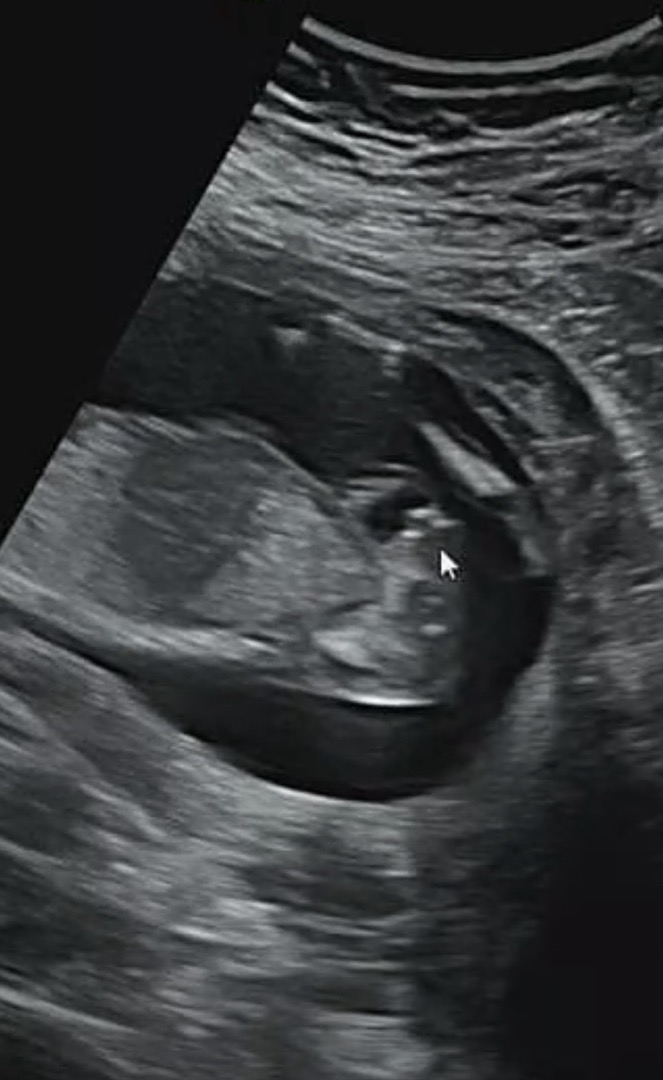

16주 성별봐주세요

아기가 잘안보여줘서 잘모르겠네요 혹시 다리쪽 보이는게 아들일까요???

16주 삼각점은 아들일꺼에요~ 저두 둘 아들맘 ㅋㅋ

아들인거 같아요!